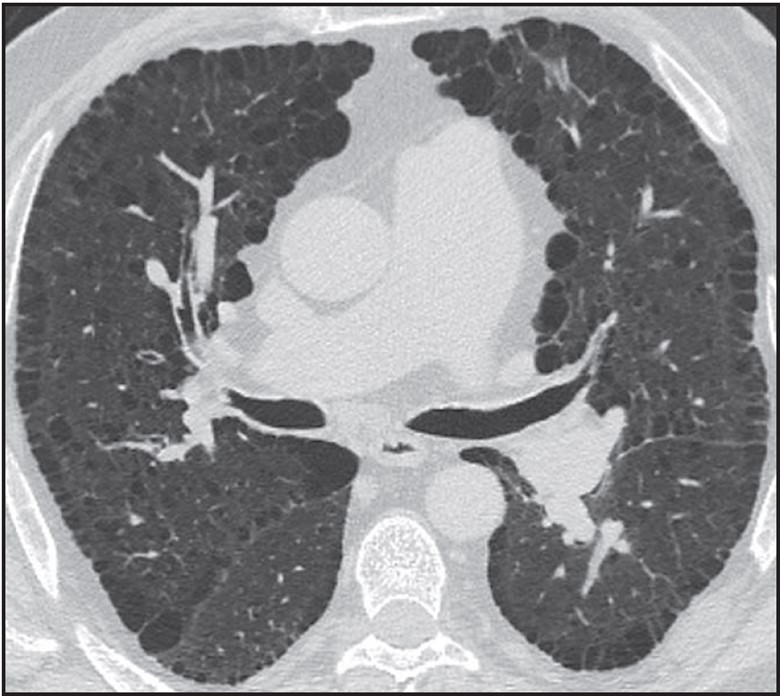

Formulating a differential diagnosis of diffuse nodular lung disease is done by identifying the distribution of nodules in relation to the pulmonary lobular anatomy. Three distributions have been described: perilymphatic, random, and centrilobular [23–25]. The perilymphatic distribution is characterized by patchy, clustered nodules that are concentrated most frequently in the peribronchovascular and subpleural interstitium. Random nodules will also be seen in the subpleural lung; however, they are not clustered but instead show diffuse homogeneous lung involvement. Centrilobular nodules are characterized by a distinct lack of nodules involving the subpleural interstitium.

The determination of the predominant pattern of diffuse nodular lung disease has several pitfalls. The perilymphatic pattern shows significant heterogeneity in the distribution of nodules. Although peribronchovascular and subpleural nodules are most typical, nodules in the interlobular septa, which also contain lymphatics, may predominate [26]. These cases may be confused for lymphangitic spread of tumor or pulmonary edema, although the thickening of the interlobular septa in pulmonary edema should be smooth, not nodular. The centrilobular interstitium is continuous with the peribronchovascular interstitium. Rarely, lymphatic diseases may have a predominance of centrilobular nodules overlapping with the centrilobular distribution (Fig. 10).

Fig. 10—Axial high-resolution CT scan shows centrilobular nodules in perilymphatic disease. Many centrilobular nodules (arrows) are present in this patient with sarcoidosis. Subpleural nodules reflect perilymphatic distribution of disease.

Although many centrilobular nodules may be present in lymphatic diseases, nodules should also be seen in the peribronchovascular or sub- pleural interstitium. This is in distinction to the centrilobular pattern in which only centrilobular nodules are present and no subpleural nodules should be seen. Lastly, diseases typically associated with a perilymphatic distribution of nodules (such as sarcoidosis) may occasionally show a fairly homogeneous involvement of the lung, mimicking a random distribution [27] (Fig. 11).

Fig. 11—Axial high-resolution CT scan shows perilymphatic distribution mimicking random nodules. Innumerable tiny nodules are present. Although pattern resembles random distribution, heterogeneous distribution in lung shows proportionally more nodules along fissures (arrows) than would be expected for random distribution.

A greater number of nodules in the subpleural or peribronchovascular interstitium may be the only clue that the distribution is perilymphatic.